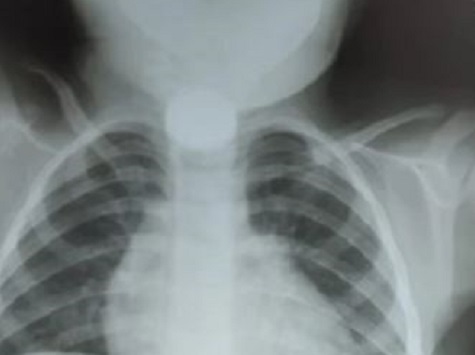

San Pedro del Ycuamandiyú: Es ist immer fatal, wenn ein Kleinkind etwas verschluckt, in diesem Fall eine Münze im Wert von 500 Guaranies.

Ärzten gelang es, im Bezirkskrankenhaus San Pedro del Ycuamandiyú eine Münze im Wert von 500 Guaranies aus dem Körper eines zweijährigen Kindes zu entfernen.

Die Fachkräfte des oben genannten Krankenhauses hatten den 2-jährigen in der Notaufnahme, sodass vor der Extraktion erst die entsprechenden Untersuchungen durchgeführt wurden.